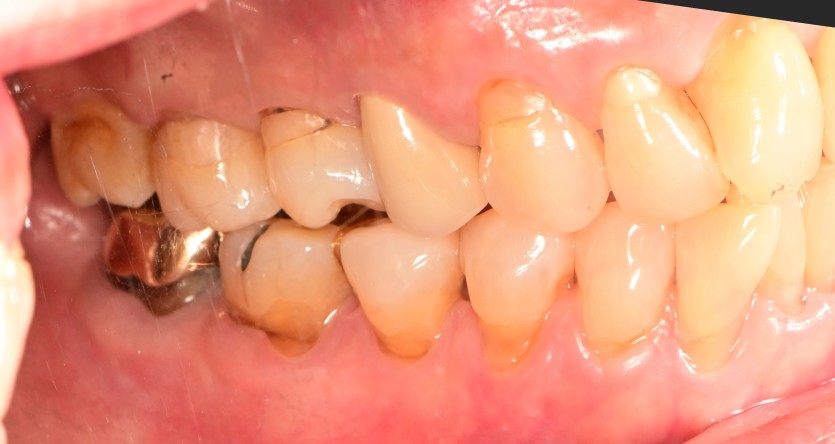

급성 턱관절염이 발생하면 발생한 쪽의 어금니가

물리지 않을 수 있습니다.

또한 턱이 한쪽으로 돌아가게 됩니다.